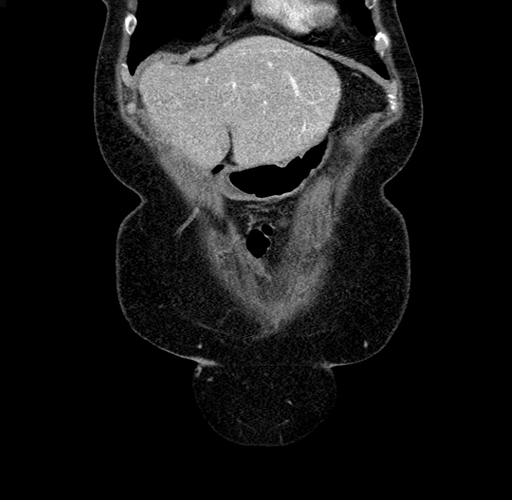

Pre-Chemo: Coronal Venous